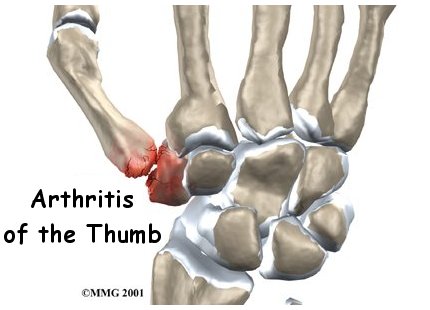

Arthritis of the Thumb

When you stop to think about how much you use your thumbs, it's easy to see why the joint where the thumb attaches to the hand can suffer from wear and tear. This joint is designed to give the thumb its rather large range of motion, but the tradeoff is that the joint suffers a lot of stress over the years. This can lead to painful osteoarthritis of this joint that may require surgical treatment as the arthritis progresses.